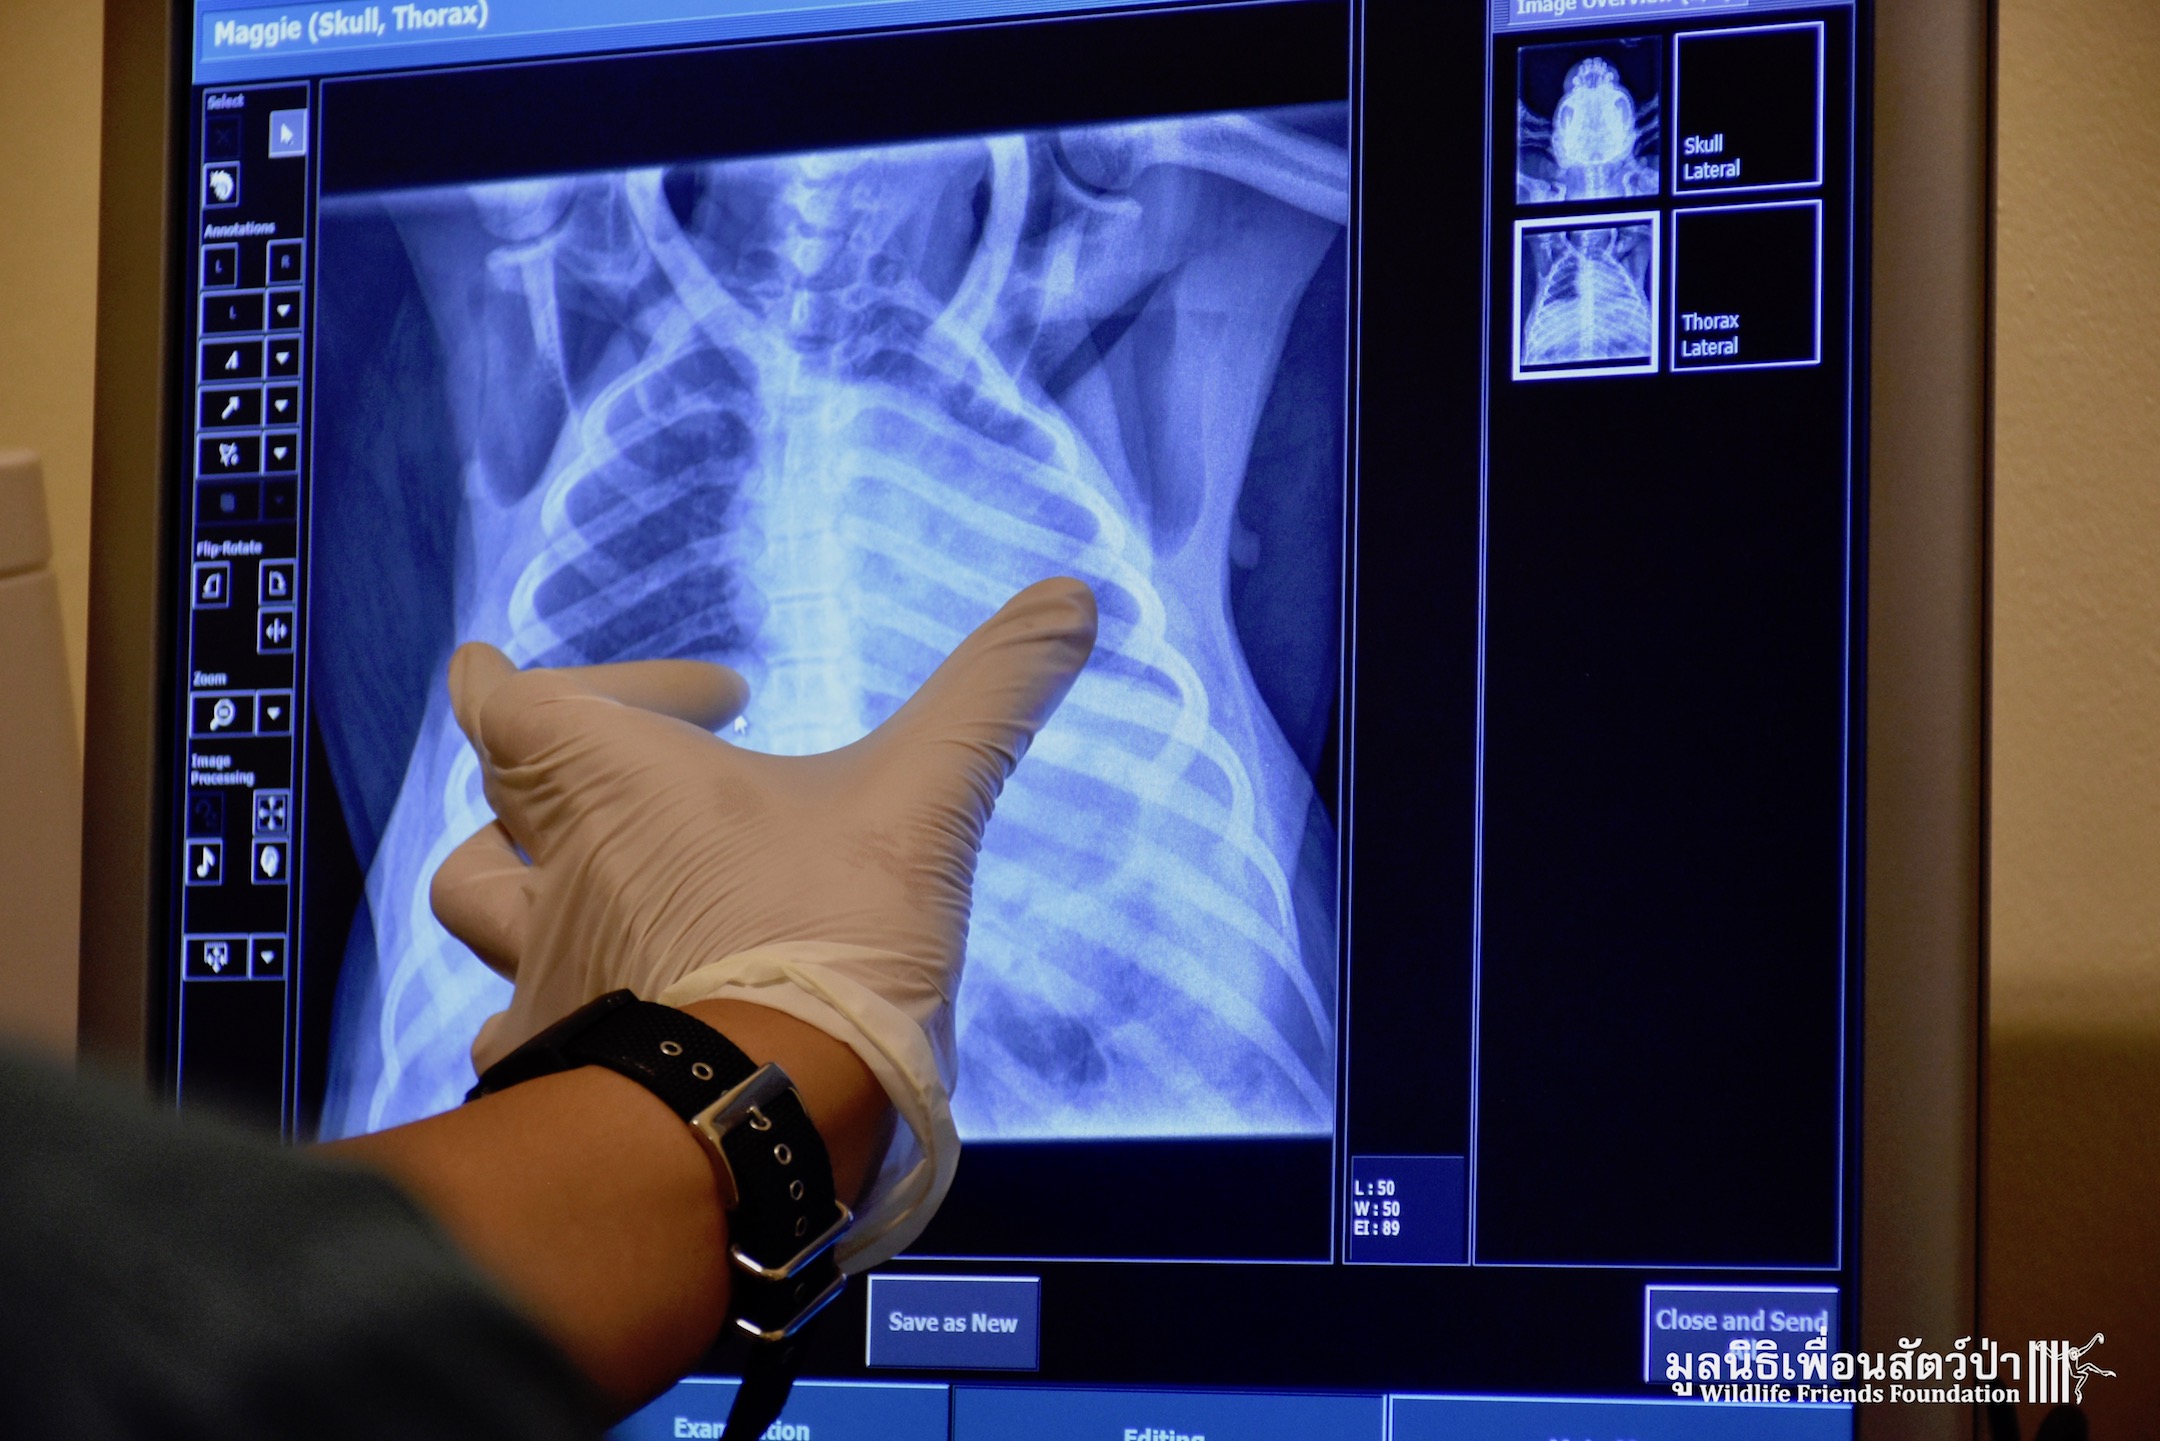

WFFT’s resident great apes, Maggie and Chico the critically endangered orangutans, are now much closer to their wonderful new home. We have moved them from their old night enclosure to a new side enclosure connected to the new huge open forest area we have created for them. During the move they made a pit stop at the WFFT Wildlife Hospital so a full health check could be performed, including a full body x-ray which was performed for the first time. This whole operation would have not been possible without the kindness and support of Mr. Mike Beets, so thank you Mike!!! And a great big thank you to the International Primate Protection League. All the team at WFFT are waiting in excitement to see these very special apes out exploring very soon. Watch this space over the coming days for an update about their first exploration expedition around their new home.